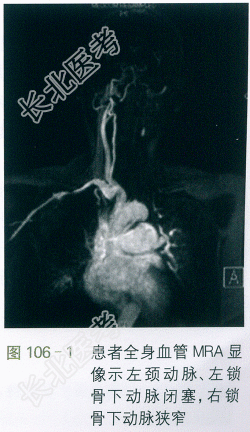

血常规、肝肾功能、尿常规、凝血功能:正常。ESR58mm/h,hsCRP7.8mg/L。RPR(-)。IgG、IgM、IgA、IgG4正常。全身血管MRA:左侧颈内动脉、双侧锁骨下动脉、左肾动脉及左股动脉中下段受累,管壁增厚伴管腔狭窄。右侧锁骨下动脉管壁增厚伴管腔明显狭窄,左侧颈总动脉及左锁骨下动脉未见显示,左肾动脉起始段及左股动脉中下段狭窄。(见图106-1)。